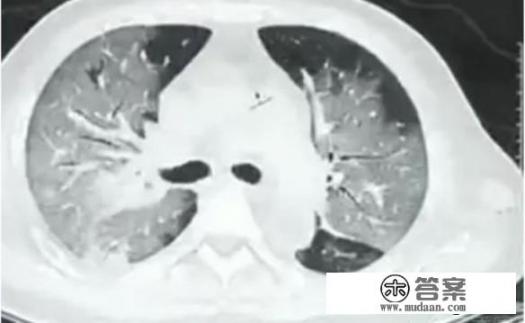

当怀疑自己被感染新冠病毒时,首先要稳定情绪,不要恐慌,根据症状进行基本判断,如果符合新冠病毒的症状,要做好防护并及时到医院就诊,如果不确定自己的症状是否由新冠病毒引起,可以先观察自己的症状,再和普通感冒、流感症状进行对比,做出基本判断,特殊时期,去医院就诊有引发交叉感染的风险,建议可以先网上咨询,再根据自己的症状自行服药,如果症状不缓解再就医。

对于是否会被隔离的问题,如果经过判断疑似或确诊感染了新冠病毒,必须进行隔离,隔离是为了对自己和社会负责,隔离环境良好,有专业人士照看,对于非湖北地区的疑似病例,需要符合一定的流行病学史和临床表现才能判定,请根据自身情况判断是否需就医或隔离观察。